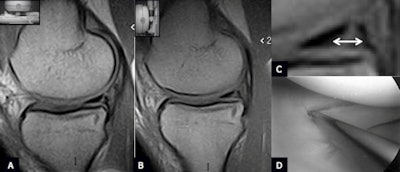

| Unstable longitudinal traumatic tear of the medial meniscus posterior horn. (A) Sagittal scan plane PD-W in the supine position shows a longitudinal tear of the posterior horn of the medial meniscus. (B) Sagittal scan plane PD-W in the weight-bearing position shows the increased intrameniscal extension of the lesion on the axial plane: See magnification from image B in C (arrow). (D) Arthroscopy confirms unstable traumatic longitudinal tear of the medial meniscus posterior horn. |

In the first group, no statistically significant anatomical modifications of shape, intensity, and position of the medial meniscus were observed between standard 1.5-tesla, dedicated supine, and upright MRI. In group A, the images acquired in the supine position (dedicated and 1.5-tesla MRI) documented in 21 cases a traumatic tear (group 2A) and in 36 cases a degenerative tear (group 2B).

"After an 82° table rotation, MRI examinations allowed evaluation of the physiological variations of the signal under physiological load, as well as of the medial meniscal position and morphology. Morphology, intrameniscal signal and measurements of the grade of medial meniscal extrusion, evaluated on both sagittal and coronal planes, did not show statistically significant differences," they wrote.

In group 2A, weight-bearing MRI showed the presence of an unstable tear in only 19 out of 36 cases. In group 2B, weight-bearing MRI showed this in only nine out of 21 cases. Arthroscopy confirmed the weight-bearing MRI diagnosis in all cases.